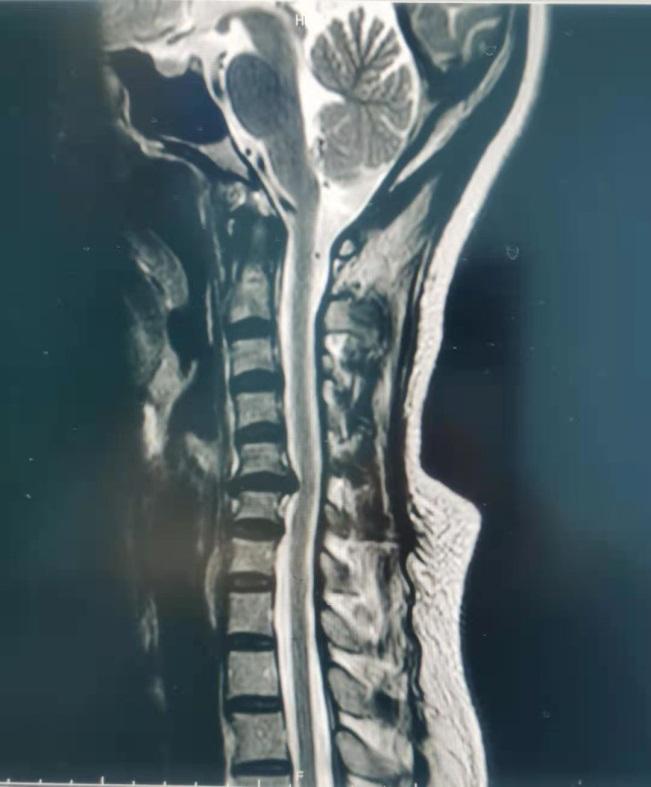

因为杨大姐的颈椎间盘突出真的挺严重了,突出的椎间盘压迫神经,要不是杨大姐能忍能坚持,换一般人早疼得受不了了。

杨大姐又想起了5年之前做腰椎微创手术的经历,抱着最后的希望赶到北京世纪坛医院疼痛科找李娟红主任看病。李娟红主任再次认真地分析了这位“老病号”病情,认为虽然病人颈椎椎间盘突出明显,症状重,年龄也偏大,体质变弱,但仍然可以进行微创治疗,这样不仅避免了全麻开刀手术的风险和可能的损害,还不影响病人的工作和正常生活。

经过充分的术前评估,疼痛专家李娟红主任为杨大姐做了颈椎脊神经根脉冲射频微创治疗,按照杨大姐的说法:都没什么感觉,就一个多小时,聊着天手术就做完了。